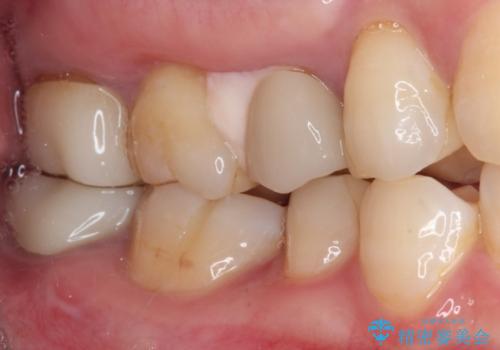

- 見た目の不揃いなセラミックと、痛みを感じる歯を気にして来院された患者様です。

右上の歯は噛んだときに何カ所か痛みを感じるとのことで、診査したところ第二小臼歯が患歯と疑われました。

患者様は他の歯にも痛みを感じるとおっしゃっていましたが、そのような所見が認められなかったため、まずは第二小臼歯を処置し、その痛みが引いた後に再診査することとしました。

痛みが引いた後、不揃いな見た目で気になっていた左下の奥歯とともにオールセラミッククラウンにて補綴治療を行うこととしました。

右上の歯は、第二小臼歯の初回処置後に痛みを感じなくなったため、他の歯については問題なしと診断しました。

将来ホワイトニングをされるとのことで、前歯よりもやや白い色合いのオールセラミッククラウンを選択されました。